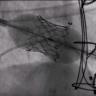

The following video shows an Edwards SAPIEN 3 TMVR implanted through the apical Certitude delivery system in a patient with severe mitral insufficiency following a bioprosthetic failure.

The authors describe their findings in a multicenter retrospective review of clinical outcomes in 64 patients with severe mitral annular calcification considered poor candidates for traditional surgical mitral valve replacement, undergoing transcatheter mitral valve implantation with a balloon expandable prosthesis.